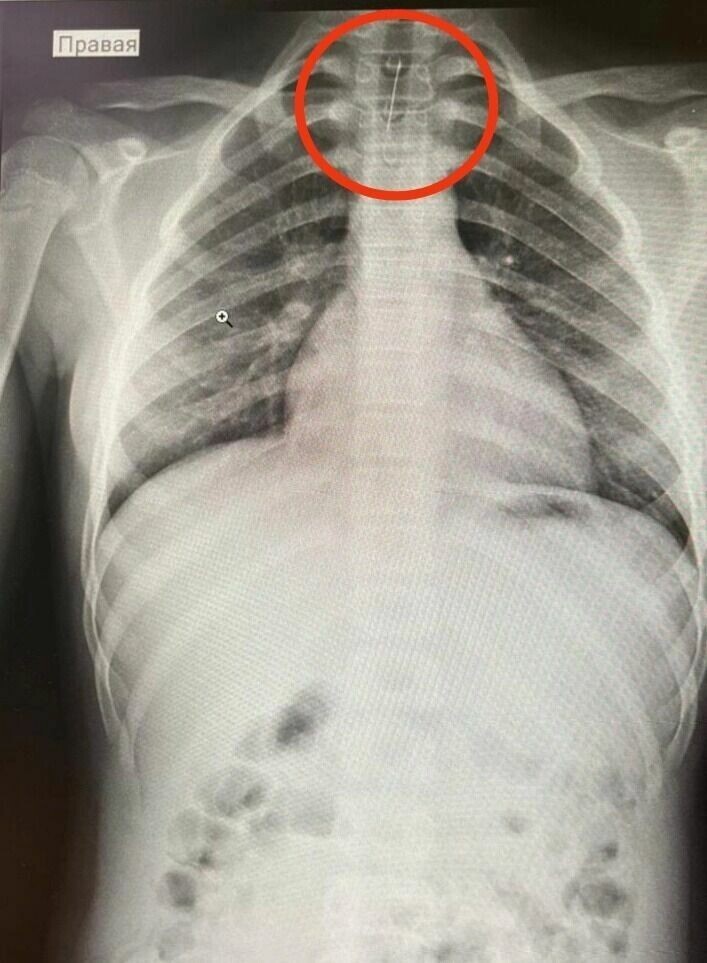

Хирург провёл осмотр пациентки, сделал ФГДС и рентген, на котором было обнаружено инородное тело в трахее. После консультации с педиатром-хирургом Республиканской детской клинической больницы по линии санавиации девочку отправили в Уфу.